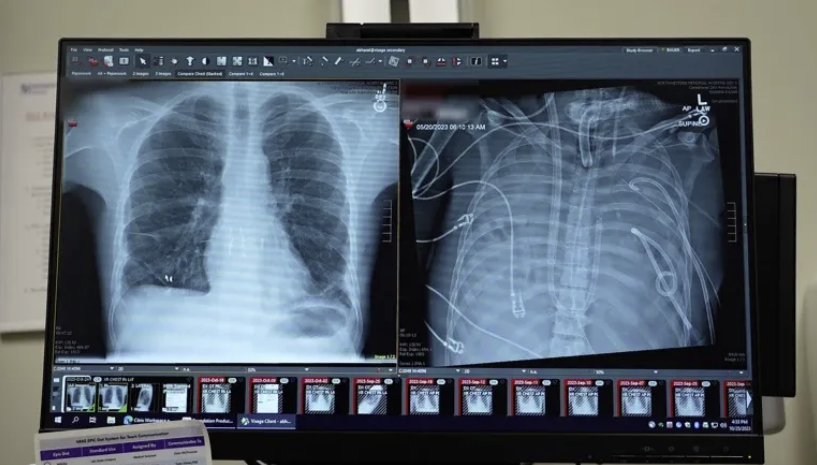

x光显示33岁患者的新肺(左)和旧肺(右)

外科医生切除了病人受感染的肺部。一个人工肺系统维持了他的生命。